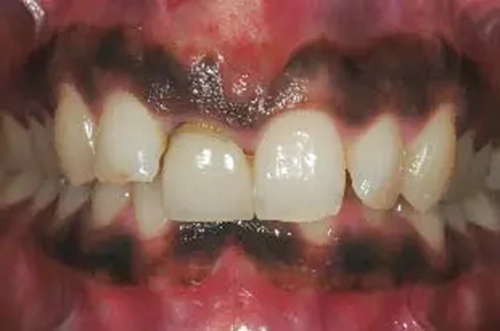

圖1、該病例顯示了厚齦生物型和中弧線形齦乳頭形態(tài)。右上中切牙由于牙根縱裂而需要拔除。由于該患牙伸長,使得軟組織量垂直向增加。牙齦色素沉著是個(gè)美學(xué)挑戰(zhàn)。

圖1、外形較大的雙側(cè)上中切牙唇側(cè)有瘺管,預(yù)后不佳,患者高笑線、薄齦生物型。